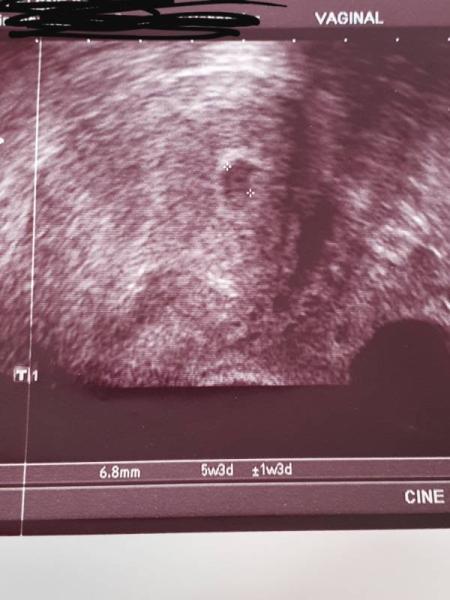

Erst einmal ruhig bleiben. Du hattest einen guten Start mit einem sehr guten HCG Wert. Ich habe gerade mein 1. Ultraschall Bild aus dieser aktuellen Schwangerschaft raus gesucht. Ich war da 5+3 und daneben steht +-1w3d mein baby war zudem Zeitpunkt zeitgerecht und mit jeder Woche lag es in der Entwicklung zurück zum Schluss 6+2 statt 7+0. Da gab es den Herzschlag und ich wurde aus der Behandlung entlassen und ich habe ängstlich gefragt, ist es nicht zu klein? Und sie gleich nein da steht doch +-6 also alles im Rahmen . 2 Wochen später war sie zeitgerecht und jetzt bin ich in der 20 ssw. Dein Wurm ist vielleicht etwas am bummeln. Ich verstehe das du Angst hast ich habe bei jedem Termin wo Krümel zurück lag gedacht "das wars" aber auch im Krankenhaus wo ich wegen einer geplatzten zyste behandelt wurde sagte man trotz icsi kann man zurück bzw weiter sein. Versuch tief durchzuatmen, mal dir keine Horror Szenarien aus. Noch ist alles drin. Bei mir musste auch gesucht werden und der Bluttest wurde bei mir bei jedem Termin gemacht um hcg und Progesteron im Auto zu behalten. Ich drücke alle Daumen hoffe du bist morgen beruhigter wenn du die Ergebnisse vom Hcg hast

Bild zu

Das ist so lieb von dir das du mir das so ausführlich erklärst!! Dein Bild schaut sehr gut aus das hatte ich nicht,...hab's leider nicht mitbekommen ...sie hat es ausgemessen was zu sehen war und war sich nicht sicher...aber es war definitiv nicht so gut sichtbar wie auf deinen Foto ich Versuche ruhig zu bleiben ich glaube auch das der HCG massiv gestiegen ist da es zuerst eine ganz helle Linie war und heute war die 2 te Linie am Test dunkel und dick Ich hatte nur einen Notkaiserschnitt und es kann sein das das krümmel in die Narbe reingerutscht ist...oder in den Eileiter...ach so ein Mist